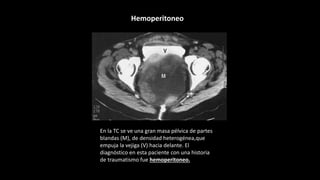

En la TC se ve una gran masa pélvica de partes

blandas (M), de densidad heterogénea,que

empuja la vejiga (V) hacia delante. El

diagnóstico en esta paciente con una historia

de traumatismo fue hemoperitoneo.

Hemoperitoneo